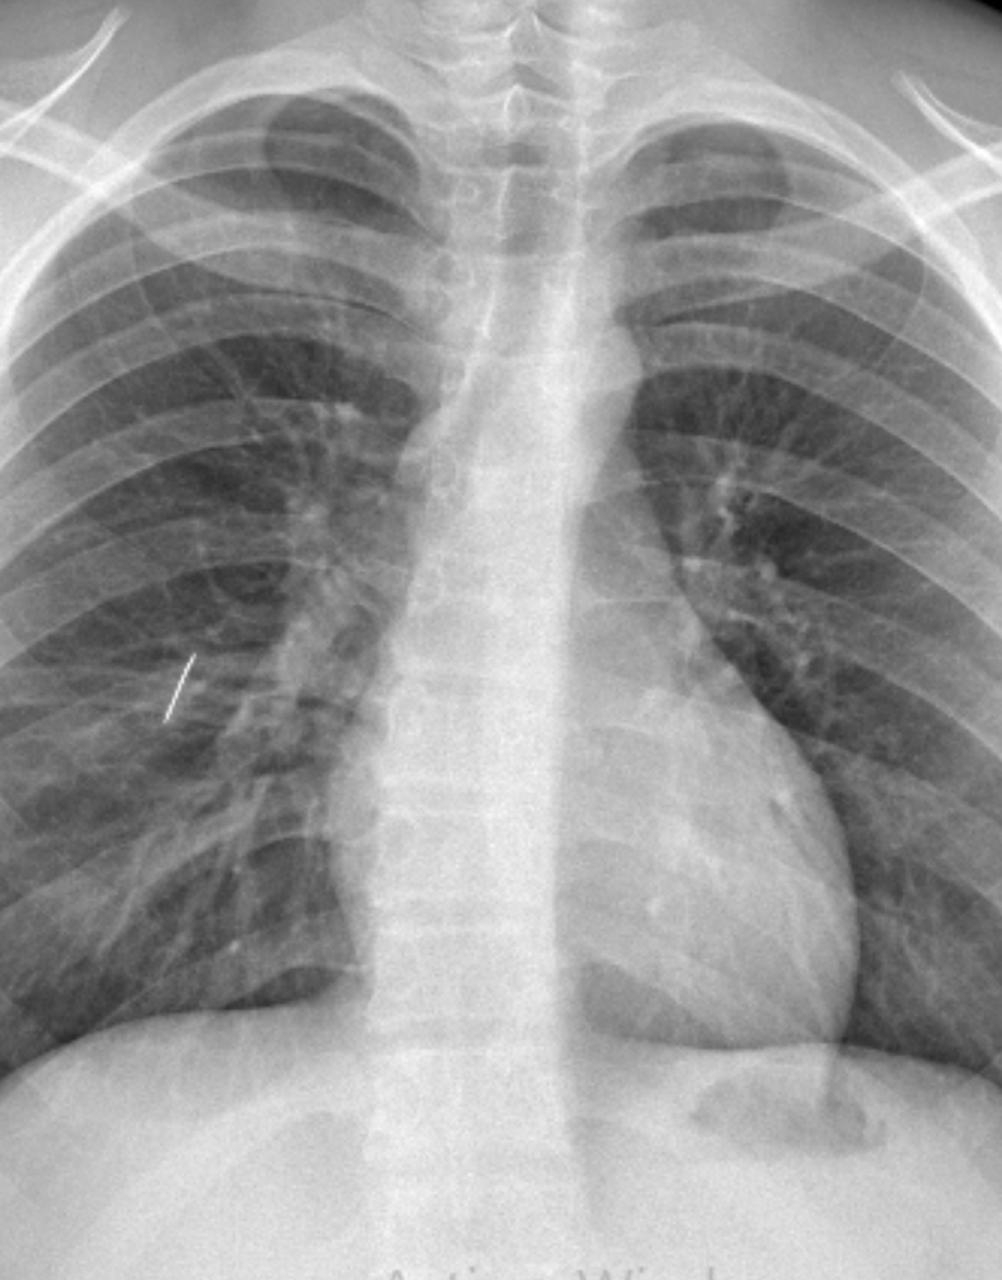

Un equipo médico del Hospital Interzonal San Juan Bautista llevó adelante una intervención quirúrgica de alta complejidad para extraer una aguja de coser alojada en el pulmón de un adolescente de 16 años, oriundo de Tinogasta, quien había sufrido un accidente doméstico.

El joven ingresó al centro de salud tras ser derivado desde su localidad de origen, luego de que un objeto metálico le provocara un trauma penetrante de tórax al apoyarse sobre una caja. Tras los primeros estudios, se confirmó la presencia de la aguja en el pulmón, lo que motivó una rápida intervención del equipo médico.

En una primera instancia, profesionales del área de Emergencias realizaron un drenaje torácico para evacuar aire, sangre y secreciones. Sin embargo, debido a que el pulmón no lograba expandirse por la presencia del objeto, se decidió avanzar con una cirugía abierta.